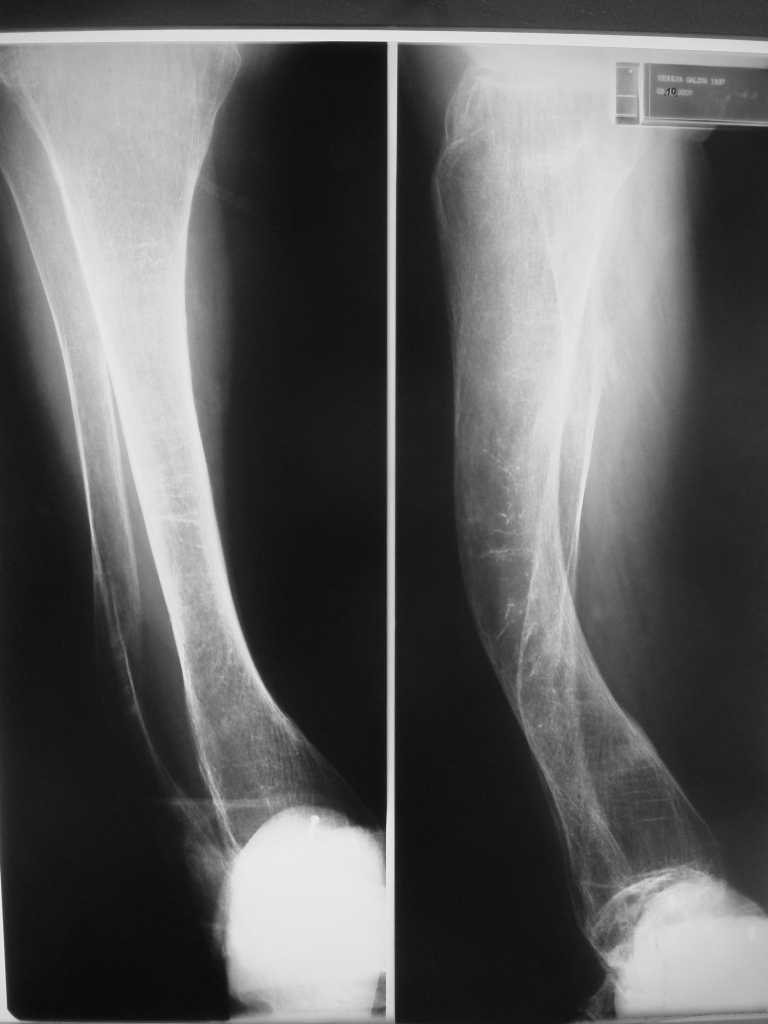

Re: Множественные переломы нижних коенечностей на фоне деформаций

Но даже при малоинвазивной методике лечения применимой для даной больной существуют следующие проблемы: выраженный остеопороз, тонкий кортикал, очень широкий канал.

Контрольные рентгенограммы прилагаю.